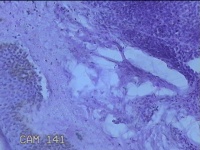

性别

男

年龄

48岁

临床诊断

皮下结节

一般病史

发现前额部结节半年余。

标本名称

前额部结节

大体所见

灰白暗红色0.8x0.3x0.2cm一块,表面带梭形皮肤0.8x0.3cm,皮下见结节0.7x0.3x0.2cm一个,切开结节呈实性,切面灰白粉红色,质软。

图1